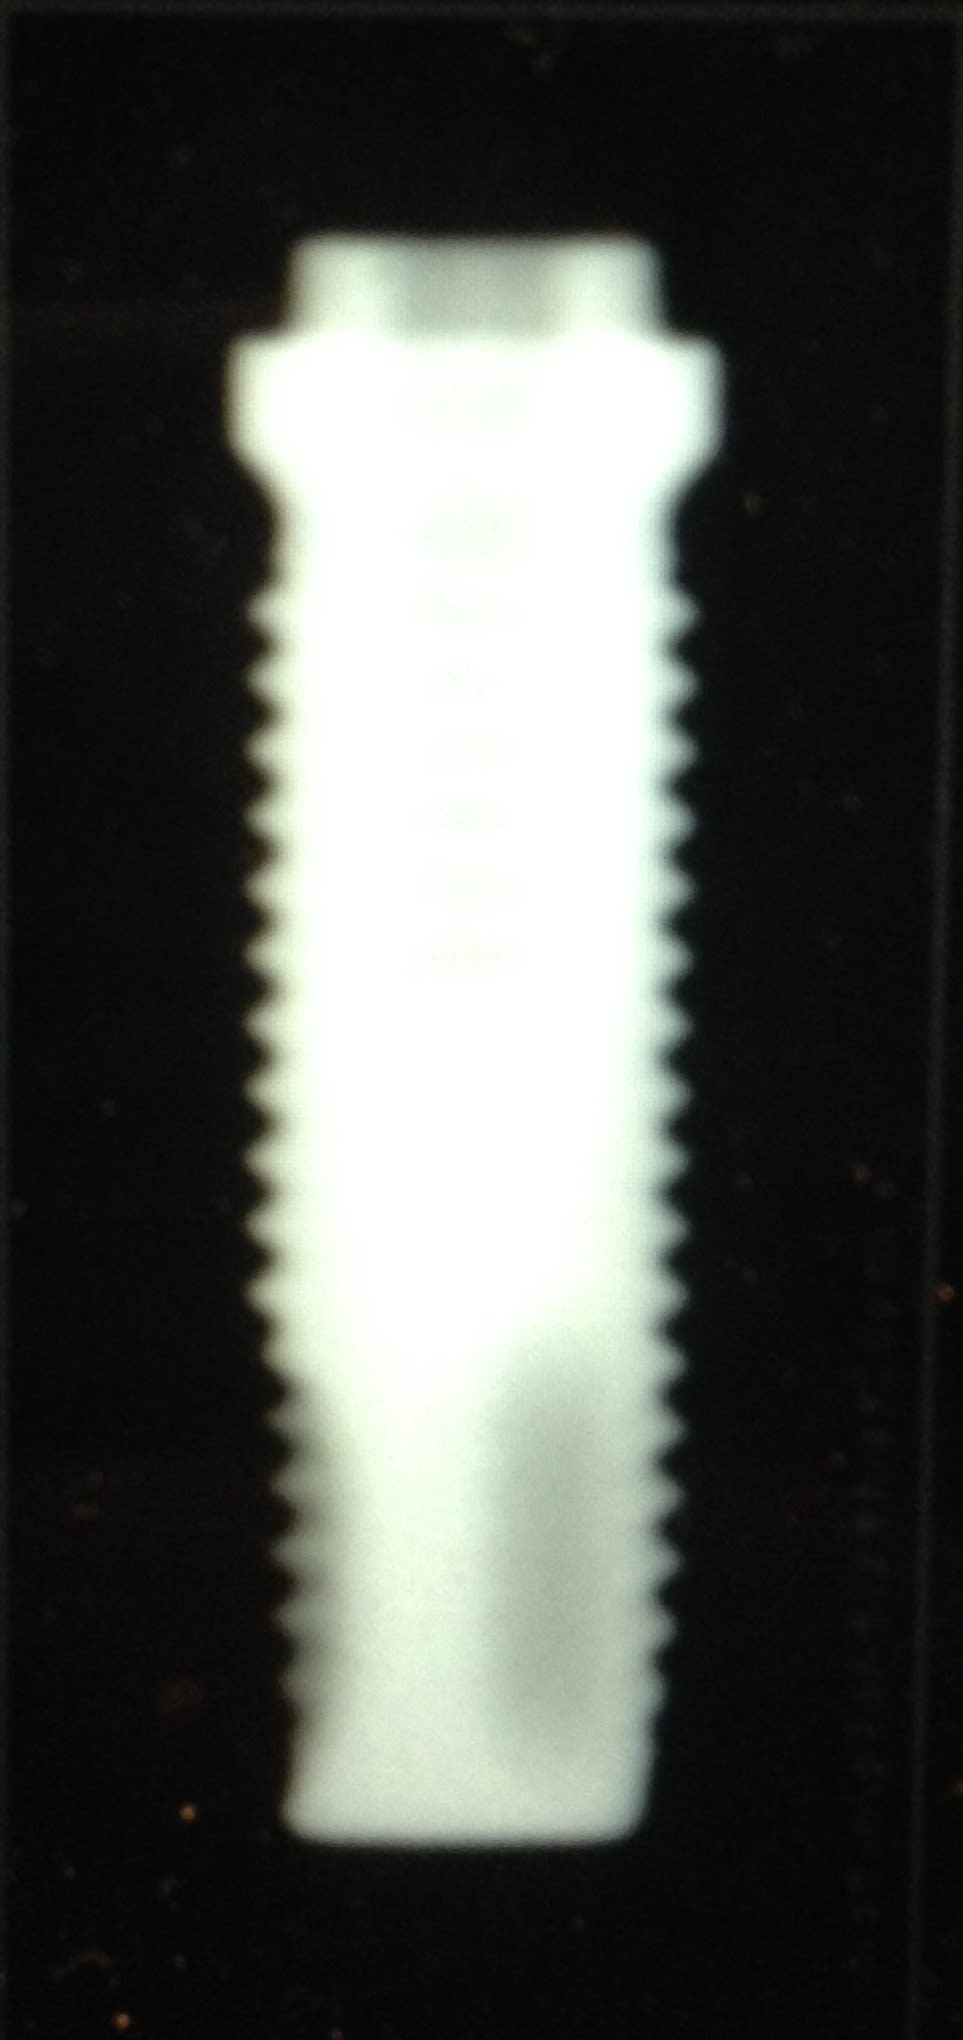

Et Les fameux Implants Branemark l'original , MK1, 2, 3, 4 ..... c'est comme les Peugeot une fois qu'ils ont trouvé Le filon , ils l'exploitent à mort 206 207 208 😊. C'est du business. Mais on remarquera que finalement Adams et d'autres avaient déjà presque tout compris bien avant En ce qui concerne la forme de l'implant et son fonctionnement . Et on se rend compte dans la 2eme moitié du siècle que Le titane supplante les autres métaux. Père de l'implantologie moderne (osseointegration + propriétés mécaniques bien meilleures pour le titane)

Img 1276 mn5sw9 - Eugenol

Img 1277 gmam2f - Eugenol

Img 1278 heox4v - Eugenol

Img 1279 cefubz - Eugenol